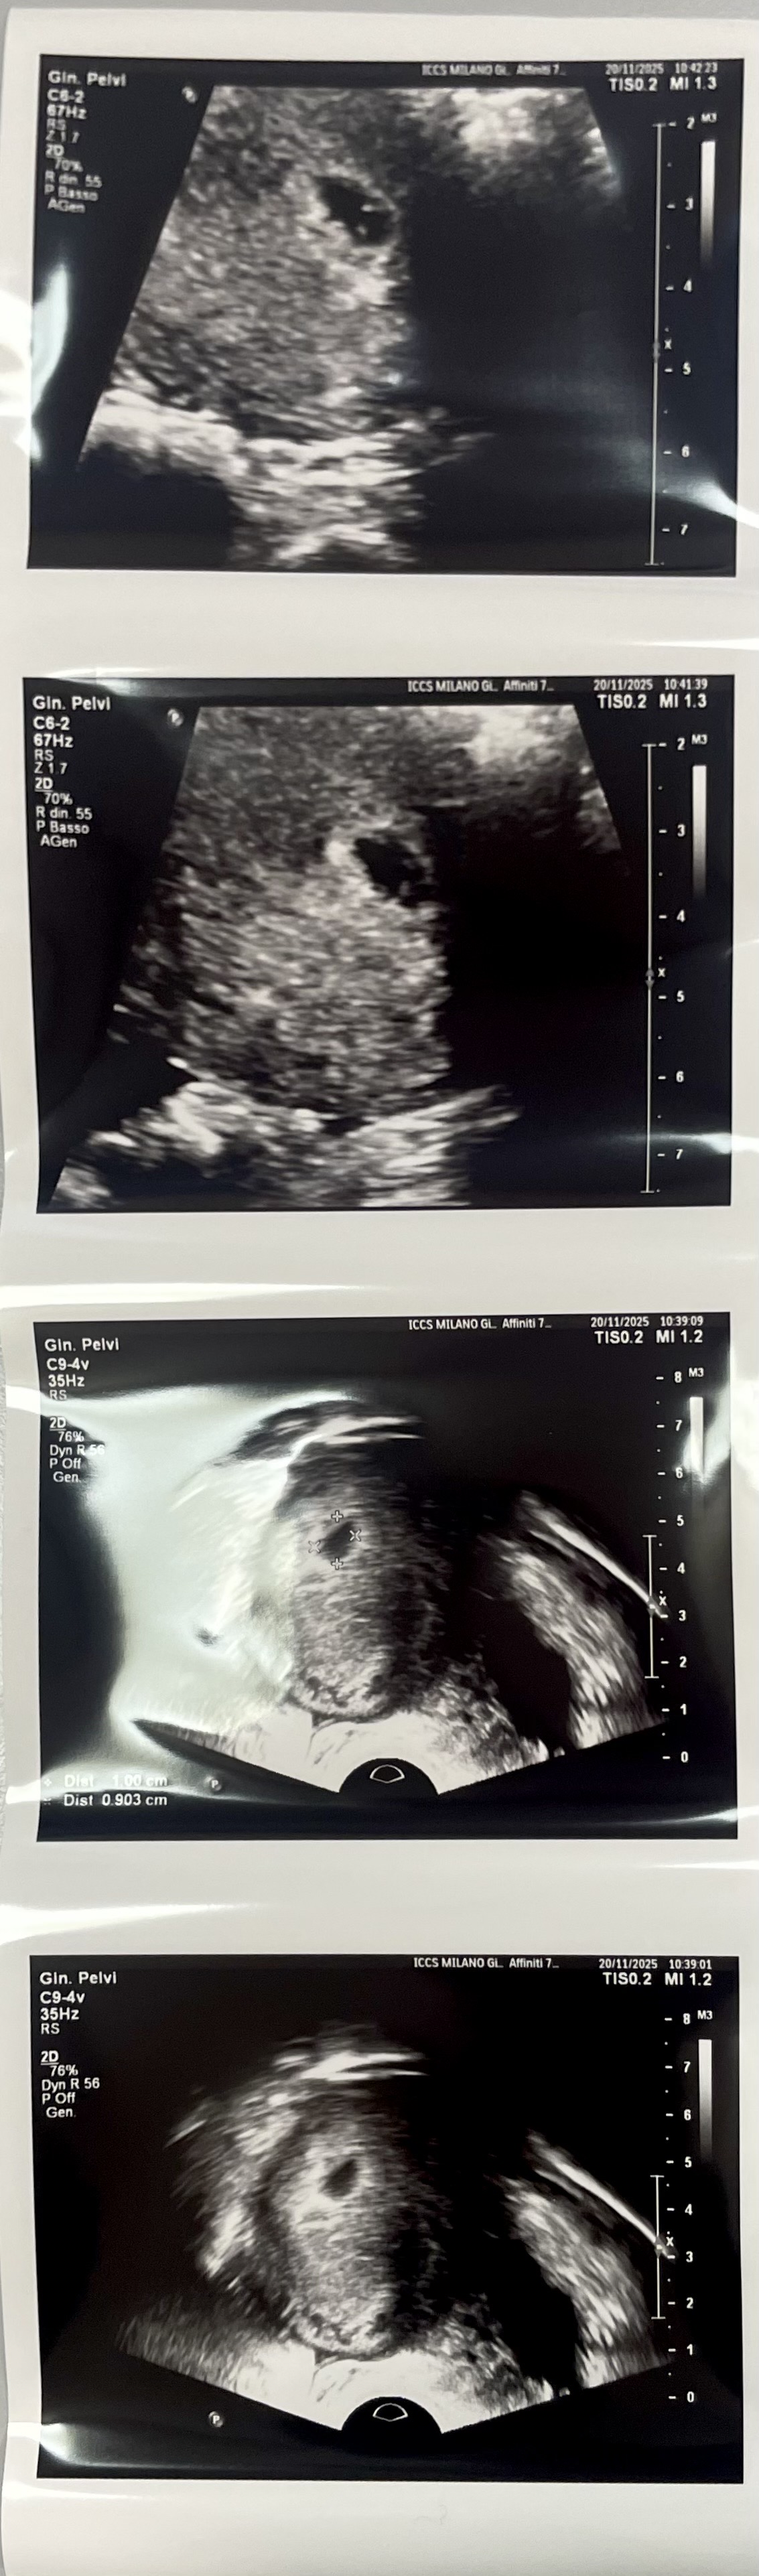

안녕하세요. 밀라노 사는 새댁이에요. 6주 아기 심장확인 후 바로 산후조리원 예약하려는데 예약이 다 찼대요😱 원래 그런건가요 그 달이 유독 몰린건가요…;; 대구이고 본가가 수성구라 본가 가까운 곳 가고싶은데 당황스럽네요